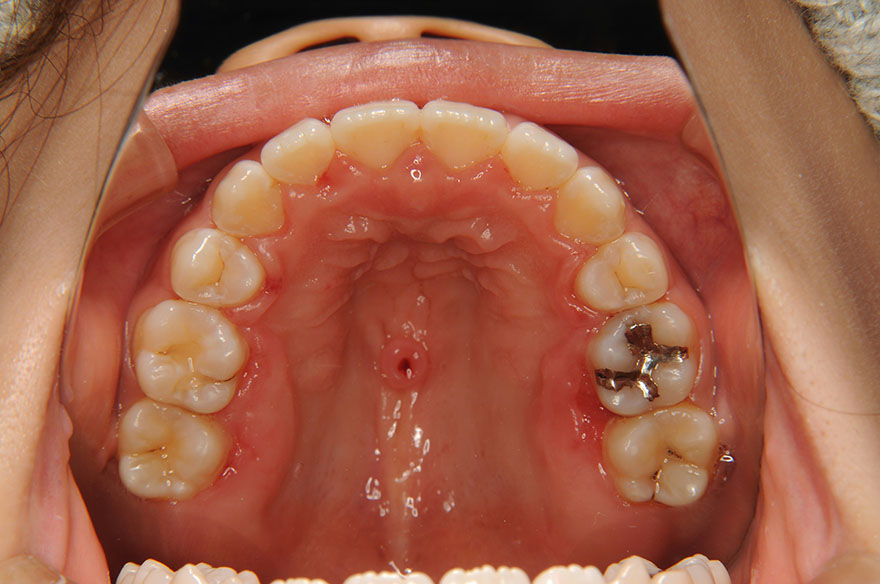

症例2(正中離開・過蓋咬合)

- ご要望・問題点すきっ歯を治したい

- 症状正中離開・過蓋咬合

- 患者さま情報21歳9ヵ月 女性

- 治療期間3年5ヵ月(スプリント使用期間6ヵ月含む)

- 治療費1,130,000円(税込)

【内訳(別途消費税)】

矯正装置料:800,000円(スプリント代含む) / 検査診断料:50,000円 / 歯科矯正用アンカースクリュー:10,000円 / 調整料:5,000円 / 保定観察料:3,000円など - 治療詳細上顎両側4番、5番、右下5番の5本欠損。上顎両側と右下第二乳臼歯、右上乳犬歯の4本乳歯残存。上顎両側2番矮小歯。顎関節症の治療のためにスプリントを使用。その後、上下ラビアルブラケット使用。右上乳犬歯を抜歯。上顎両側1番、2番をコンポジットレジンにて形態修正。

- リスク・副作用残してある乳歯は動揺、脱落した場合は親知らずの移植あるいはデンタルインプラントにする必要があります。コンポジットレジンで形態修正した上顎1番、2番は変色する可能性があるため、いずれ本格的な補綴治療が必要となります。噛み合わせを長期間安定させるためには、保定治療が大切です。